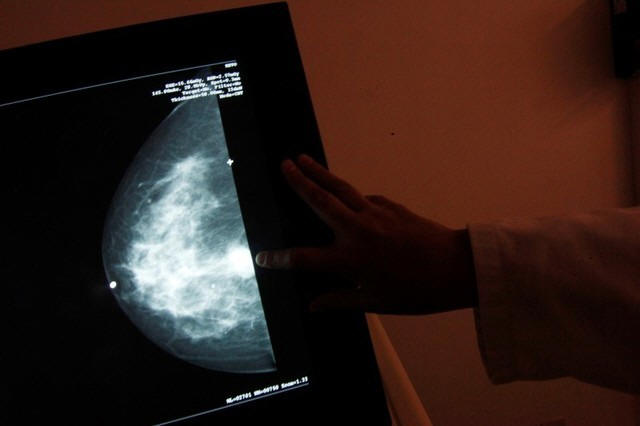

Mammograms, too, may be problematic, they write, citing Swiss data

showing that these tests avert just one breast cancer death for

every 1,000 women screened.